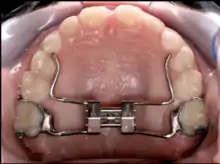

Palatal expansion

Palatal expansion can be best achieved using a fixed tissue born appliance. Removable appliances can push teeth outwards but is less effective at maxillary sutural expansion. The effects of a removable expander may look the same as they push teeth outwards but should not be confused with actually expanding the palate. Proper palate expansion can create more space for teeth as well as improve both oral and nasal airflow.